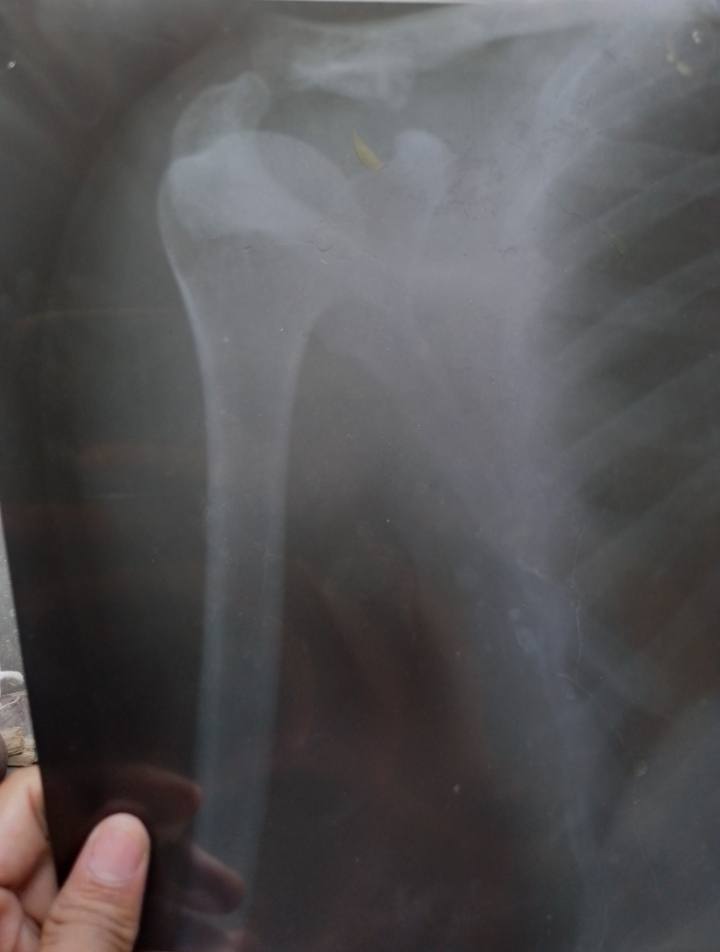

लगभग 1 साल पहले चक्कर आने की वजह से मैं गिर गया था जिससे कंधे में चोट लग गई और कंधे में उभार भी आ गया| उस समय मैने ज़्यादा ध्यान नहीं दिया| वर्तमान में कंधे में दर्द रहता है और कंधे में जो उभार है उसे भी कम करवाना है| क्या इसका इलाज हो सकता है अगर हो सकता है तो कितना खर्चा आएगा| मै मेरठ जिले का निवासी हूं|